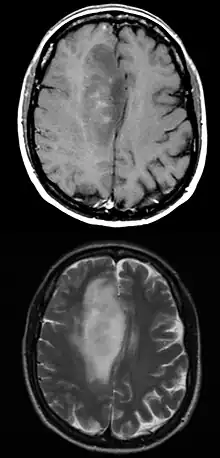

Axial post-contrast T1 (top) and T2 (bottom) weighted MRI showing an IDH1 mutant frontal lobe glioblastoma with sparse enhancement despite large size.

When viewed with MRI, glioblastomas often appear as ring-enhancing lesions. The appearance is not specific, however, as other lesions such as abscess, metastasis, tumefactive multiple sclerosis, and other entities may have a similar appearance.[42] Definitive diagnosis of a suspected GBM on CT or MRI requires a stereotactic biopsy or a craniotomy with tumor resection and pathologic confirmation. Because the tumor grade is based upon the most malignant portion of the tumor, biopsy or subtotal tumor resection can result in undergrading of the lesion. Imaging of tumor blood flow using perfusion MRI and measuring tumor metabolite concentration with MR spectroscopy may add diagnostic value to standard MRI in select cases by showing increased relative cerebral blood volume and increased choline peak, respectively, but pathology remains the gold standard for diagnosis and molecular characterization.